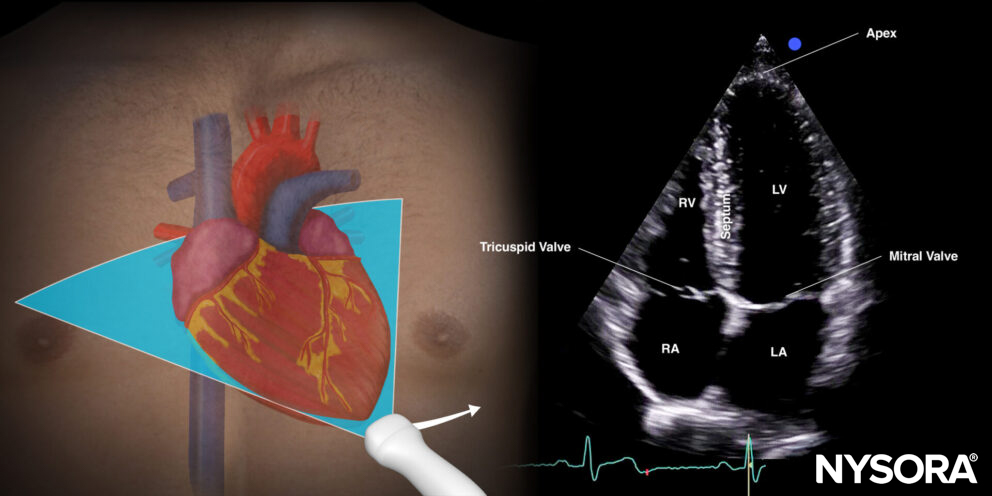

Apical four-chamber view (A4C)

Transducer position and sonoanatomy of the apical four-chamber view.